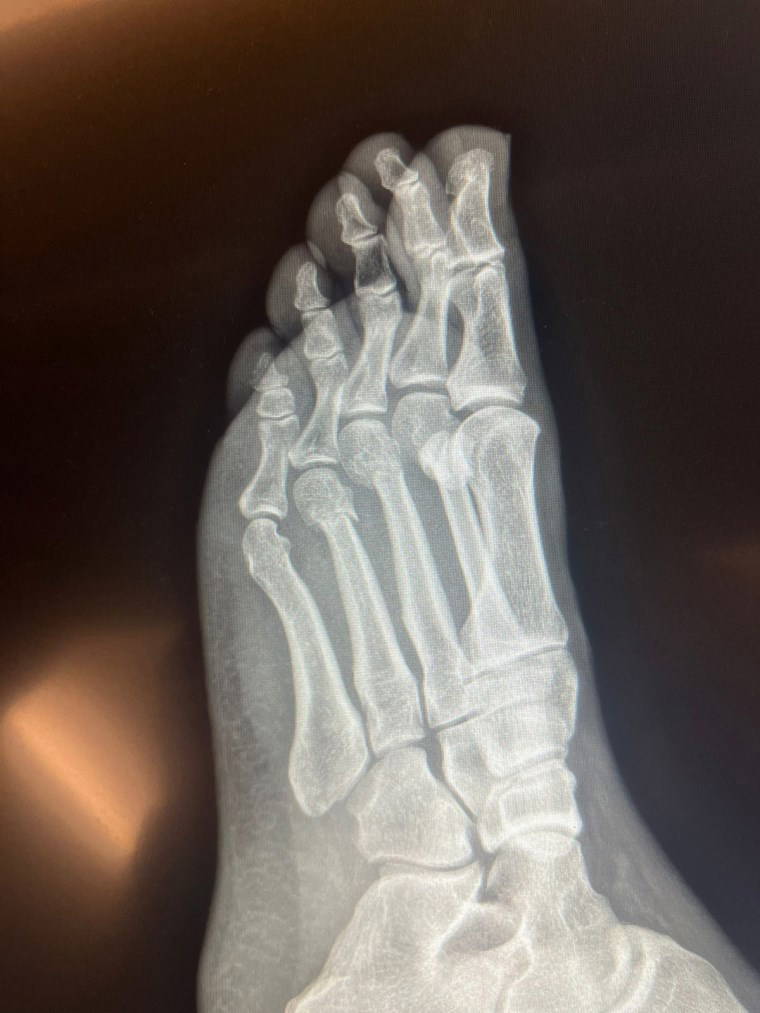

RÖNTGEN FİLMLERİNİ PAYLAŞTI

Röntgen filmlerini paylaşan CHP lideri, iddialara ilişkin olarak “FETÖ’cü hesapların yaydığı bir yalan, daha sonra üzerine eklenerek, boyutlandırılarak kasıtlı olarak devam ettirildi” dedi.

'PARMAK KEMİKLERİ KIRIK'

CHP Genel Başkanı Özgür Özel’in “Herkes inceleyebilir” dediği filmleri inceleyen Ortopedist Prof. Dr. Tarık Yazar da şu değerlendirmeleri yaptı:

“Sayın Özgür Özel’in röntgen filmlerini incelediğimizde parmak kemiklerindeki kırıkları gördüm. Açık bir yara olmaması bir şanstır. Yani, dışarıya kan akmamış. Röntgende yara olup olmadığı her zaman görülmez. Ancak, Özgür Bey’in röntgenini incelediğimizde yine de şanslı olduğunu gördüm. Biz buna ‘şanslı kırık’ deriz. Aslında tam kırık da diyemeyiz. Ayrılmamış, kemiğin özelliği bozulmamış.

İyileşme yeteneğinin fazla olduğu bir bölgede kırık var. Şanslı tarafı kanlanmanın kuvvetli olduğu bir bölgede kırık gördüm. Bilgisayarlı tomografiyle takibi uygun olur. Tedaviye doğru başlanmış. Mutlaka iyileşecektir. Kullandığı ayak desteği gayet doğru bir seçim. Üç aya kalmaz tam iyileşme gerçekleşir. Lütfen bir daha düşmesin."